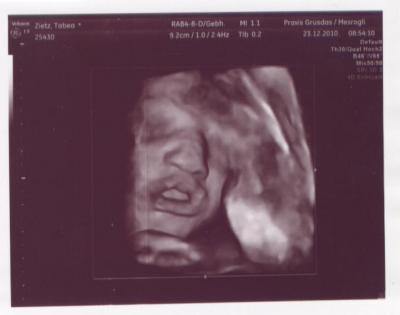

...von meinem Engel :)

oh eine süsse nase+mund..echt sweet der-die kleine